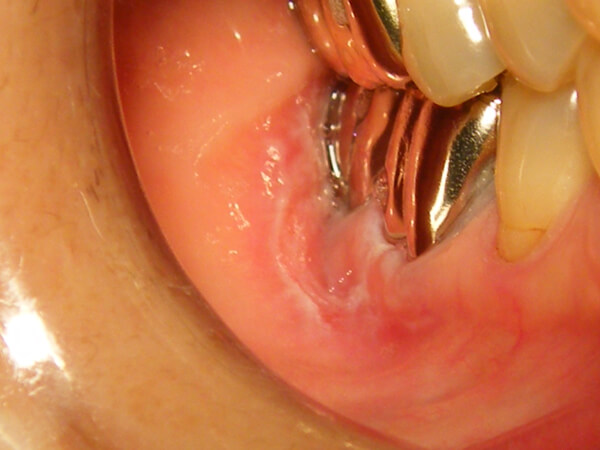

扁平苔癬

皮膚や粘膜にできる、角化性で炎症を伴う難治性の病変で、白い粘膜疹(ねんまくしん)がレース状にみられ、周囲が赤くなったりします。